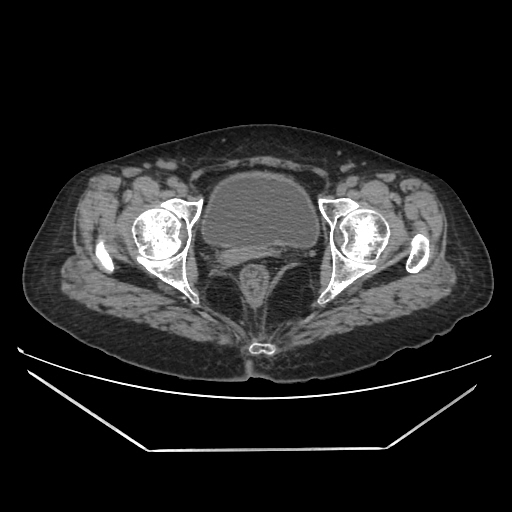

A CT abdomen revealed a left adrenal cortical tumor.

Her abdominal X-ray also reveals a right renal stone although she never complained of renal colic.

CT images: